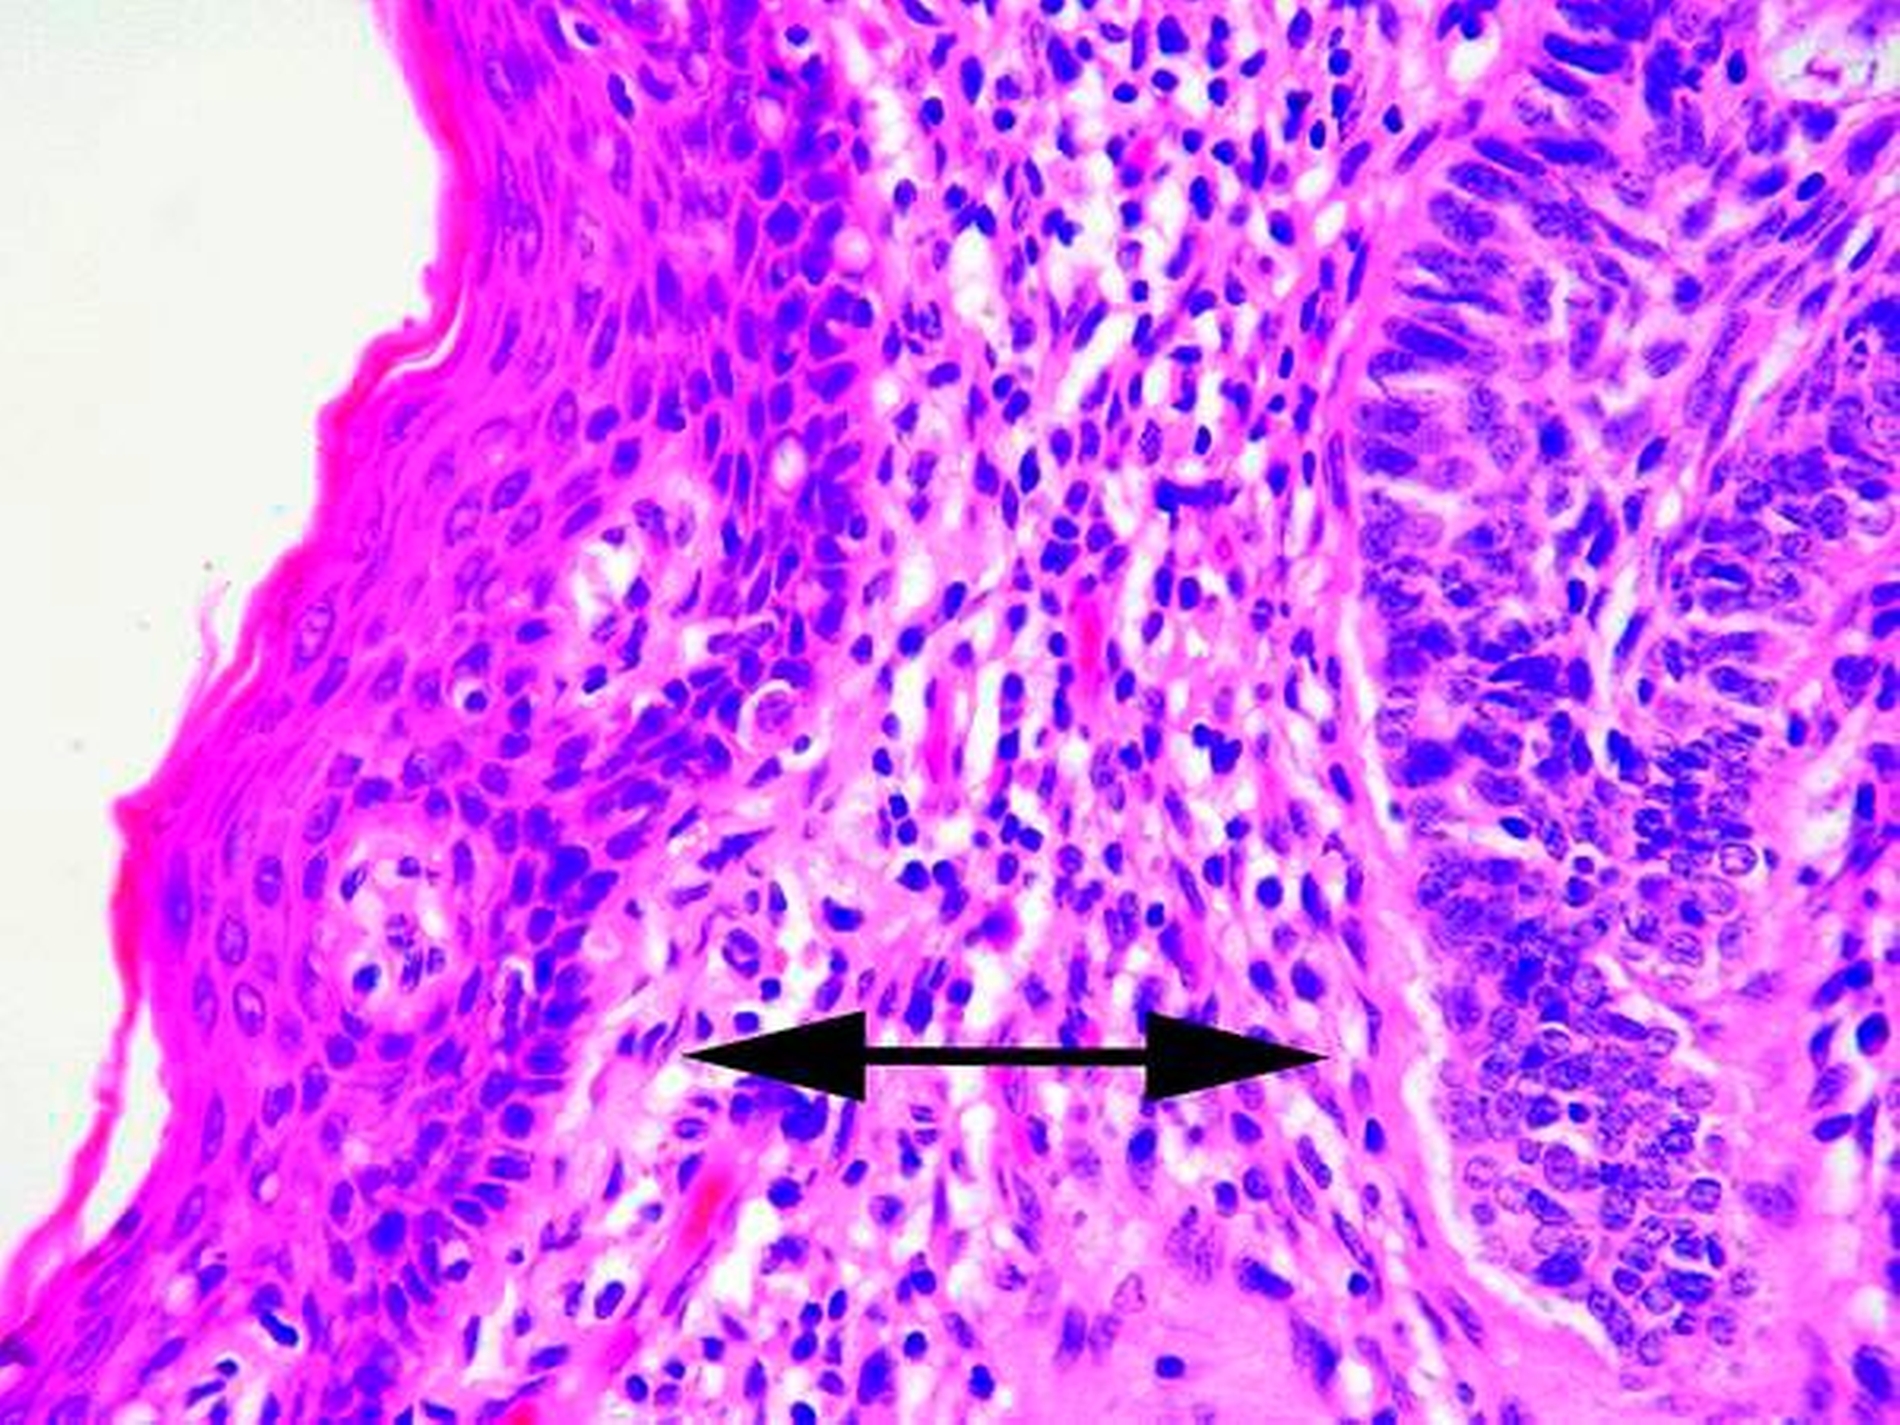

Die histopathologische Aufbereitung des Gewebes (Abbildungen 3 bis 6) bestätigte dabei die Diagnose eines Basalzellkarzinoms.

Die Diagnose wird vornehmlich klinisch gestellt und dann histopathologisch verifiziert. Es gibt unterschiedliche Subtypen, wie zum Beispiel das noduläre, das superfizielle, das sklerodermiforme Basalzellkarzinom und dann den Ulcus rodens und den Ulcus terebrans. Am häufigsten ist das noduläre Basalzellkarzinom als scharf abgegrenzter und flach erhabener Tumor, der gelblich-rötlich imponiert und häufig einen perlschnurartigen Randsaum aufweist, mit den typischen Teleangiektasien, die von peripher nach zentral ziehen. Das sklerodermiforme Basalzellkarzinom unterscheidet sich hiervon vornehmlich durch die weitaus schlechtere Abgrenzbarkeit. Bei Bestehen der Karzinome über einen längeren Zeitraum können diese ulzerieren (Ulcus rodens) und in der Folge auch tiefer liegende Strukuren zerstören (Ulcus terebrans) [Hauschild A et al., 2012].